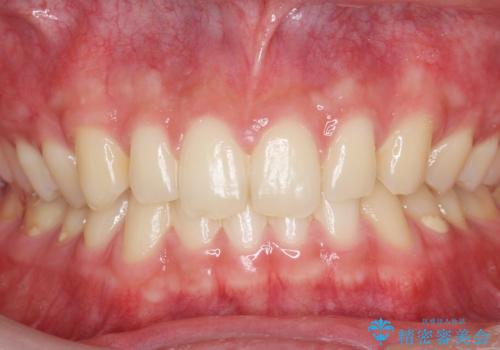

ナイトガードで歯ぎしり予防

- 歯ぎしりが気になるとの事で来院。

しっかりしたナイトガードが欲しいとの事だったので自費のナイトガードのご案内をしました。

ナイトガードは夜寝ている時、無意識に歯ぎしりをして歯がすり減ることを防ぐことがあります。また、歯が割れたり欠けたりするのも防いでくれます。